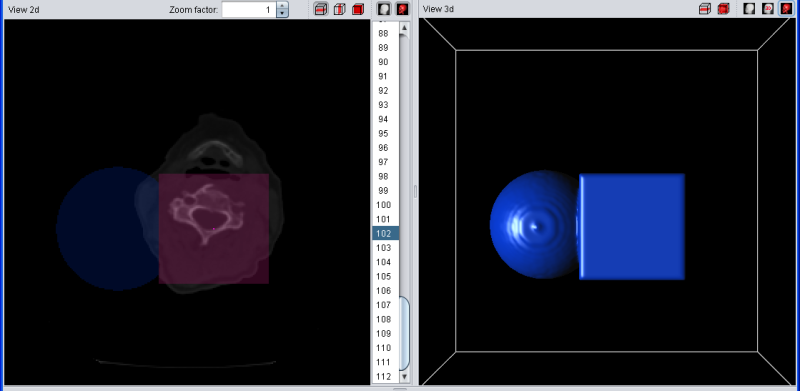

Again the example with a blue segment. If the current selection overlaps with the (red)) temporary selection, the overlapping regions are drawn in purple. If the selection is added to the segment, all red voxels turn purple because they now belong to the segment and the selection at the same time. If add, remove, copy left or copy right are pressed when no segment is selected in the list, nothing happens.

|

| Selection (red) was added to blue segment |